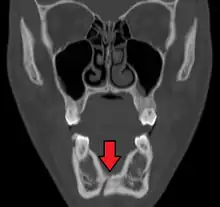

Computed tomography

Computed tomography is the most sensitive and specific of the imaging techniques. The facial bones can be visualized as slices through the skeletal in either the axial, coronal or sagittal planes. Images can be reconstructed into a 3-dimensional view, to give a better sense of the displacement of various fragments. 3D reconstruction, however, can mask smaller fractures owing to volume averaging, scatter artifact and surrounding structures simply blocking the view of underlying areas.

- Towne's view of a bilateral condyle fracture. White arrow is a fracture on the neck of the condyle. Black arrow shows the condyle pulled to the medial. The same injury can be seen on the opposite side